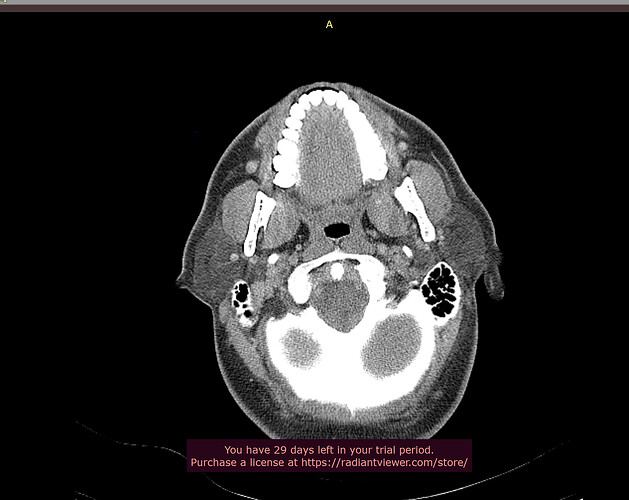

Typically, in the context of vascular ES, the most relevant view is of C1 in the axial view. I’ve attached my own imaging to help you know what to look for. It’s the top vertebrae with a white circle in the top middle:

Hey all thanks, will take a look at the video shortly, in the meantime here’s the axial view, I think.

It’s hard to see, but I believe your your right IJV is wedged between your posterior digastric and C1. The right styloid is not in contact with anything, at least at this level.

Left IJV appears to have some compression against C1. Left styloid is not present at this level.

You have a crazy amount of calcification in your neck, @jalexy12. I hope Dr. Nakaji will help you! Did you by chance look into Dr. Cognetti, too, since he’s in your state?